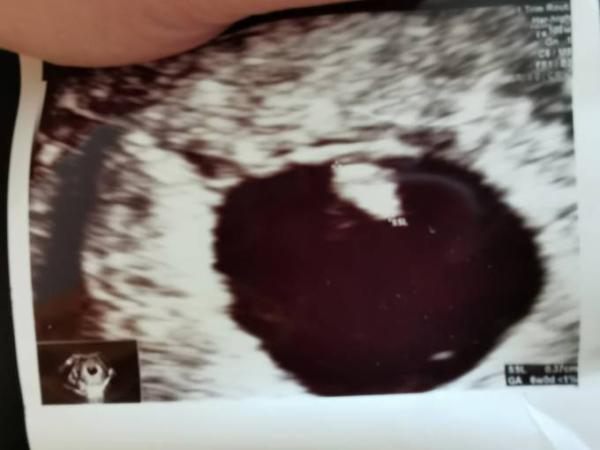

Nachdem mein Gynäkologe mich letzte Woche noch eine Woche zurück gesetzt hat durfte ich heute das erste mal den Herzschlag sehen! Das ist alles so Aufregend und ich weiß garnicht wo mir der Kopf steht. Bis zum positiven Test war eigentlich klar das ich höchstens noch 1-3 mal Hundemama werde und Kinder so ziemlich garnicht in Frage kommen. Morgen muss ich es meiner Chefin aufgrund von BV erzählen, bin aber Gott sei Dank noch bis nächste Woche Dienstag einschließlich AU (Das Autofahren hat keinen Sinn gerade).

Bild zu 2. FA Termin - Forum für Januar - Mamis